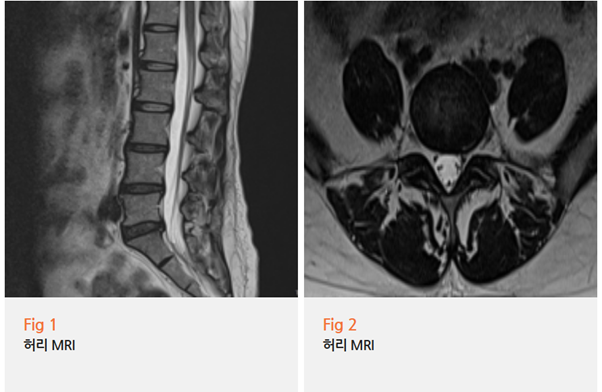

MRI 결과를 보는 순간, 역시나였습니다.

그림3.png 촬영 일시: 2025.06.11

L5-S1 추간판 탈출증. 그것도 왼쪽으로.

"보세요, 여기 이 부분이 신경을 누르고 있죠?

이게 바로 왼쪽 종아리로 가는 신경이에요."

환자분은 화면을 보시더니 놀라워하셨습니다.

정말 신기해하시면서도 한편으론 안도하시는 표정이었어요.

드디어 원인을 찾았으니까요.